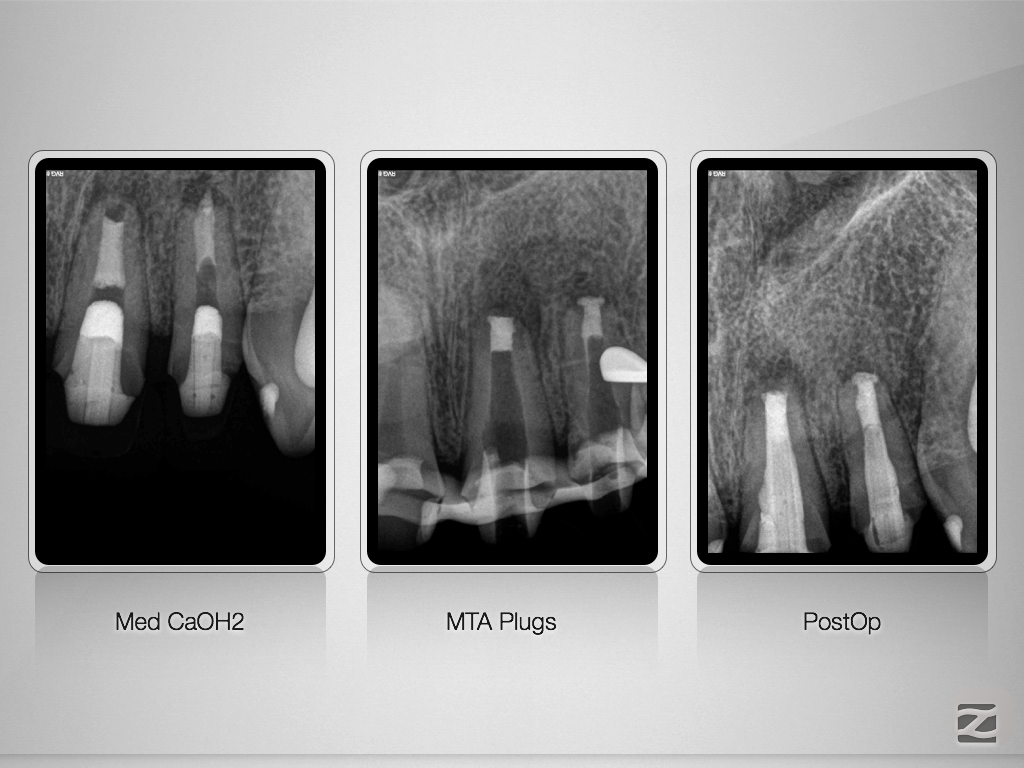

21 22 D.009

Rasche Heilung